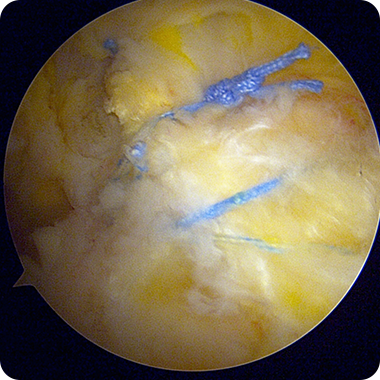

특수 앵커와 봉합사를 이용해

끊어진 힘줄을 본래의 위치로

단단히 고정합니다.